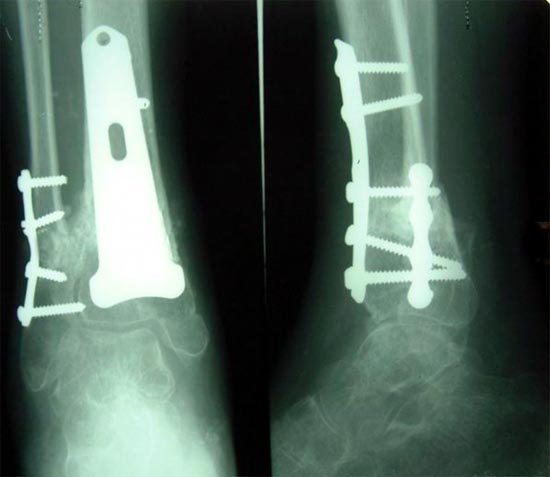

病例四、患者男性,65岁,胫骨下段骨不连2年。我们采用钢板提供支撑力,植如患者自体骨髓细胞经与松质骨和骨生长因子复合物,骨折在9个月后愈合。